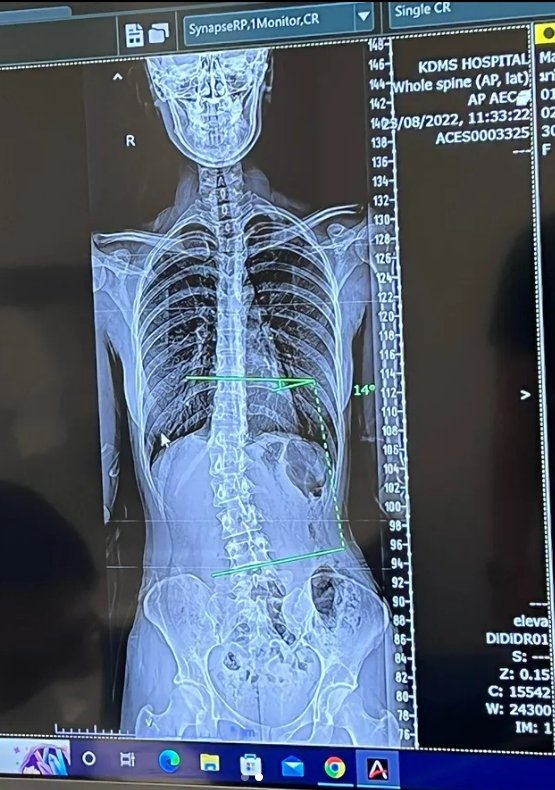

ภาพเอ็กซเรย์กระดูกสันหลังเผยให้เห็นกระดูดคด อย่างชัดเจนลงอินสตาแกรมส่วนตัว

“เคล็ดลับเอวเอส.. วัยรุ่นกระดูกคด จริงๆ รู้ตัวมาหลายปีแล้วว่ากระดูกสันหลังคด เคยตรวจมาก่อน คุณหมอก็บอกว่าไม่ได้ต้องทำอะไร วันนี้ลองมาตรวจอีกสักที สรุปก็คล้ายเดิมฮะ คุณหมอบอกว่า 14 องศาไม่ได้อันตราย และด้วยอายุขนาดนี้ไม่น่าคดเพิ่มแล้ว คุณหมอบอกว่าไม่ต้องทำอะไรค่ะ ใช้ชีวิตไปปกติได้เลย ออกกำลังกายสม่ำเสมอเพื่อให้กล้ามเนื้อแข็งแรง การจะทำให้มันกลับมาตรง คือทำไม่ได้นะคะ เพราะร่างกายเราปรับไปกับโครงสร้างของเราแบบนี้ไปแล้ว และการจัดกระดูกไม่ช่วยอะไรค้าบ”

นอกจากนี้ ส้ม ยังได้อัพเดตผ่านทางไอจีสตอรี่อีกว่า… “คุณหมอบอกว่าใช้ชีวิตตามปกติได้เลย ไม่ได้คดมากจนต้องผ่าตัด อายุขนาดนี้ไม่น่าคดเพิ่ม ไม่กระทบการใช้ชีวิต ส่วนการให้กลับมาตรง หมอก็พูดตรงๆ ว่าทำไม่ได้”